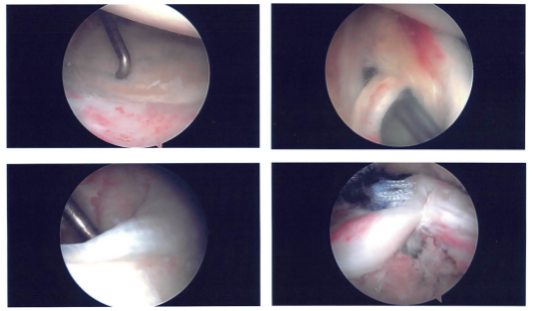

Examination of the glenohumeral joint showed a large rotator cuff tear. It also showed partial tearing and inflammation of the biceps’ tendon. Decision was made to not do the biceps and do a mini-open biceps tenodesis later.

Examination of the cartilage showed grade 1 osteoarthritic changes of the glenoid surface. There was fraying of the labrum, which was debrided with the use of a shaver. There was fraying of the subscapularis tendon, which was also debrided with the use of the shaver.

The arthroscope was inserted into the subacromial space. Subacromial bursectomy was performed with the shaver. This was followed by acromioplasty with the use of Coblation wand followed by a 6.0 burr incising the acromial spur, osteoarthritis of the AC joint was also present, which was again cleaned with the use of a Coblation wand followed by 6.0 burr excising about a centimeter of the distal clavicular through the posterior as well as anterior superior portal.

A lateral entry portal was made for the repair of the rotator cuff. The debridement of the rotator cuff was done. Also, the superior surface of the head of humerus was cleaned and debrided with the use of burr for the preparation for the repair of the rotator cuff.

Intraoperative images